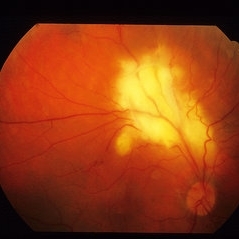

Toxocara Granuloma

Jun 4 2014 by Henry J. Kaplan, MD

Toxocara granuloma in the macula OS. #1

Condition/keywords: toxocara granuloma